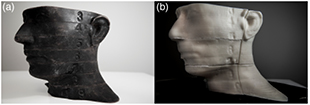

A qualitative comparison of the anthropomorphic phantom ('patient') and the 3D printed phantom is illustrated in figure 2. The Jaccard index for the external geometry was determined to be 0.956 and the Dice Similarity Coefficient was determined to be 0.973. This indicates a good match between geometries.

Figure 2. Qualitative comparison of (a) an anthropomorphic phantom, the 'patient' in this example, and (b) the 3D printed model. Note in (b) the coronal and axial film planes can be seen in the 3D printed phantom which can be set by the clinician. Also, the slice section numbers of the anthropomorphic phantom are preserved in the 3D printed model, which is remarkable considering the phantom was scanned with 3 mm CT slice thicknesses.

The proposal of constructing a patient geometry using a 3D printer is feasible in a commercial 3D printer environment. Previously, ABS has been shown to be an acceptable phantom material for dosimetric measurements (Kumar et al 2009). The main area for improvement is the time needed to construct a custom phantom. The current printer uses a 0.4 mm diameter nozzle to extrude the ABS plastic. Other FDM based 3D printers offer a larger diameter nozzle which could reduce the time needed to print a phantom; conversely, other methods of rapid prototyping are also being considered. Additionally, the printer layer height used in this work was 0.3 mm; we propose an even lower resolution would still provide acceptable quality with potential further reduction in printing time and this is a region of future work. In figure 2, it can be seen that a high level of detail is preserved in the 3D printed phantom.